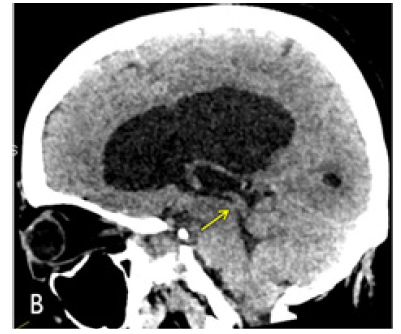

CT Brain was performed using a 128 slice Siemens Somtam Definition Edge scanner. Axial images were obtained with 5mm and 1mm slice thickness. Using the 3D MPR function on McKesson Radiology PACS station, reconstructions were performed. The sagittal reconstruction images demonstrated obstructive hydrocephalus with AW/D (Figure 1B).

Figure 1B: Sagittal reconstruction from Axial 1 mm CT slices. Dilated lateral and third ventricles with normal appearing fourth ventricle. Yellow arrow points to the AW/D, best seen in this image 1B.

MRI brain was performed in a 3T Siemens Vireo magnet. The additional axial CISS 3D sequence was obtained with isotropic 0.6 x 0.6 x 0.6 voxels taking 7.18 minutes. Sagittal and Coronal reconstructions clearly demonstrated the AW/D Despite the Motion ArtiFact (Figure 2B) (Figure 2C).